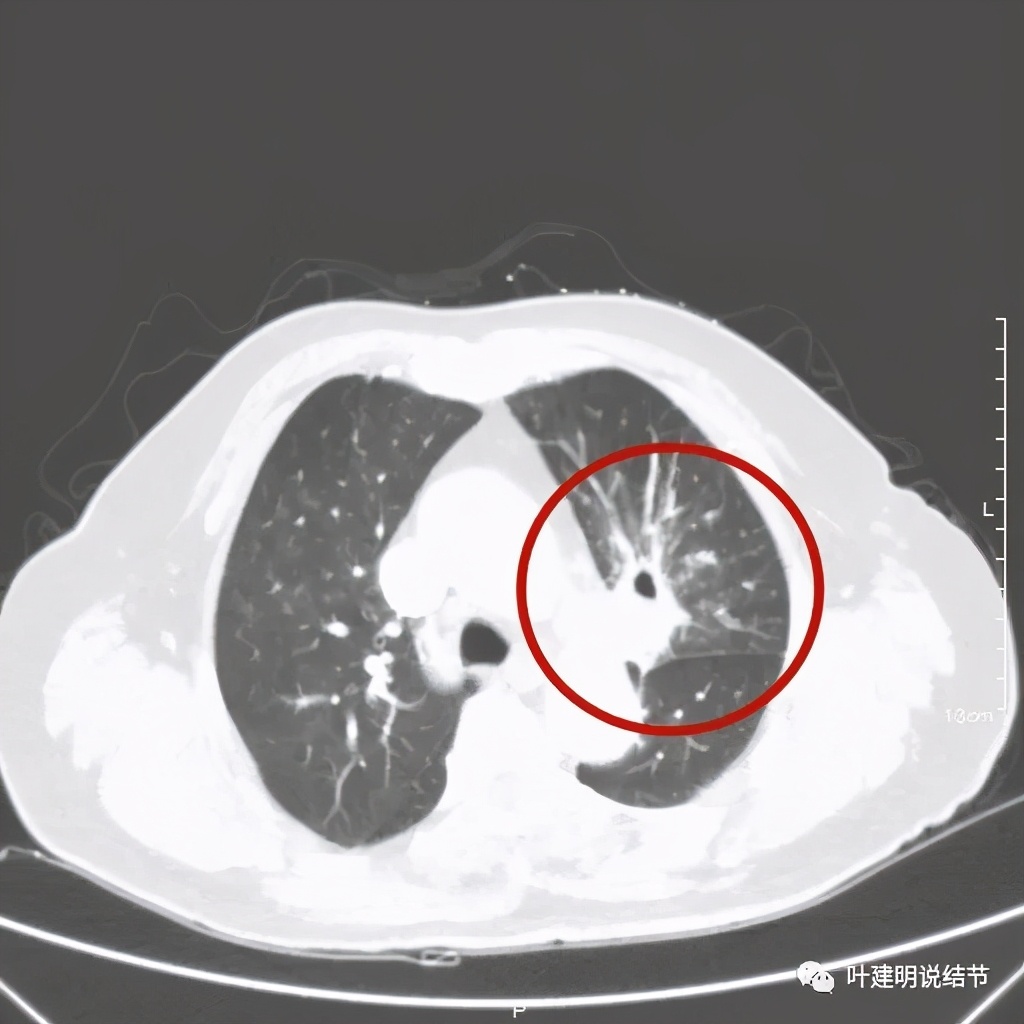

肺窗见原左上叶巨大占位已经明显缩小,甚至几乎不见了!而且上图示左上叶支气管清晰可见,内壁变光滑。纵隔窗增强又是如何的呢?